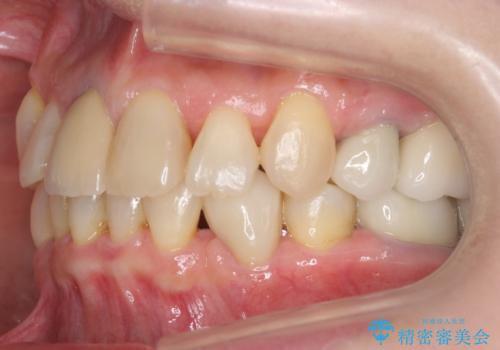

50代女性 八重歯を矯正治療 歯並びの中等度のがたつき

- 八重歯の矯正を希望されて来院。

歯は入りきらないため、通常の抜歯矯正を行いました。

詰め物や被せ物のやり替えも併せて行っているため、治療期間を比較的短縮できました。